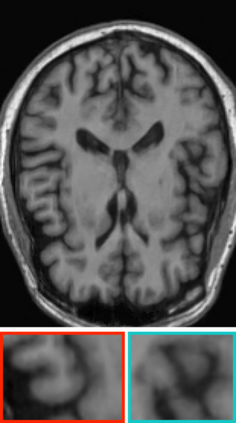

Deep neural networks for medical image reconstruction are traditionally trained using high-quality ground-truth images as training targets. Recent work onNoise2Noise (N2N) has shown the potential of using multiple noisy measurements of the same object as an alternative to having a ground truth. However, existing N2N-based methods cannot exploit information from various motion states, limiting their ability to learn on moving objects. This paper addresses this issue by proposing a novel motion-compensated deep image reconstruction (MoDIR) method that can use information from several unregistered and noisy measurements for training. MoDIR deals with object motion by including a deep registration module jointly trained with the deep reconstruction network without any ground-truth supervision. We validate MoDIR on both simulated and experimentally collected magnetic resonance imaging (MRI) data and show that it significantly improves imaging quality.